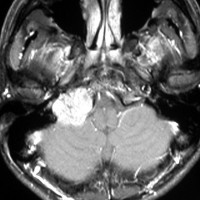

左は1991年,右は2006年のMRI画像です。15年間で腫瘍のサイズは変わっていません。

1991年に50代の女性にみつかったものでした。黄色に示したルートで摘出できないわけではありませんが,右後頭部が腫れてきたという訴えとホルネル症候,軟口蓋麻痺しかなかったので,何も治療しないでほっておきました。2016年まで25年間観察し続けました。症状の悪化は全くなく元気に暮らしておられます。グロームス腫瘍はある一定の年齢になると増大しないという性質を持っている良性腫瘍です。これを大々的な頭蓋底外科手術で摘出するするという愚を犯してはなりません。